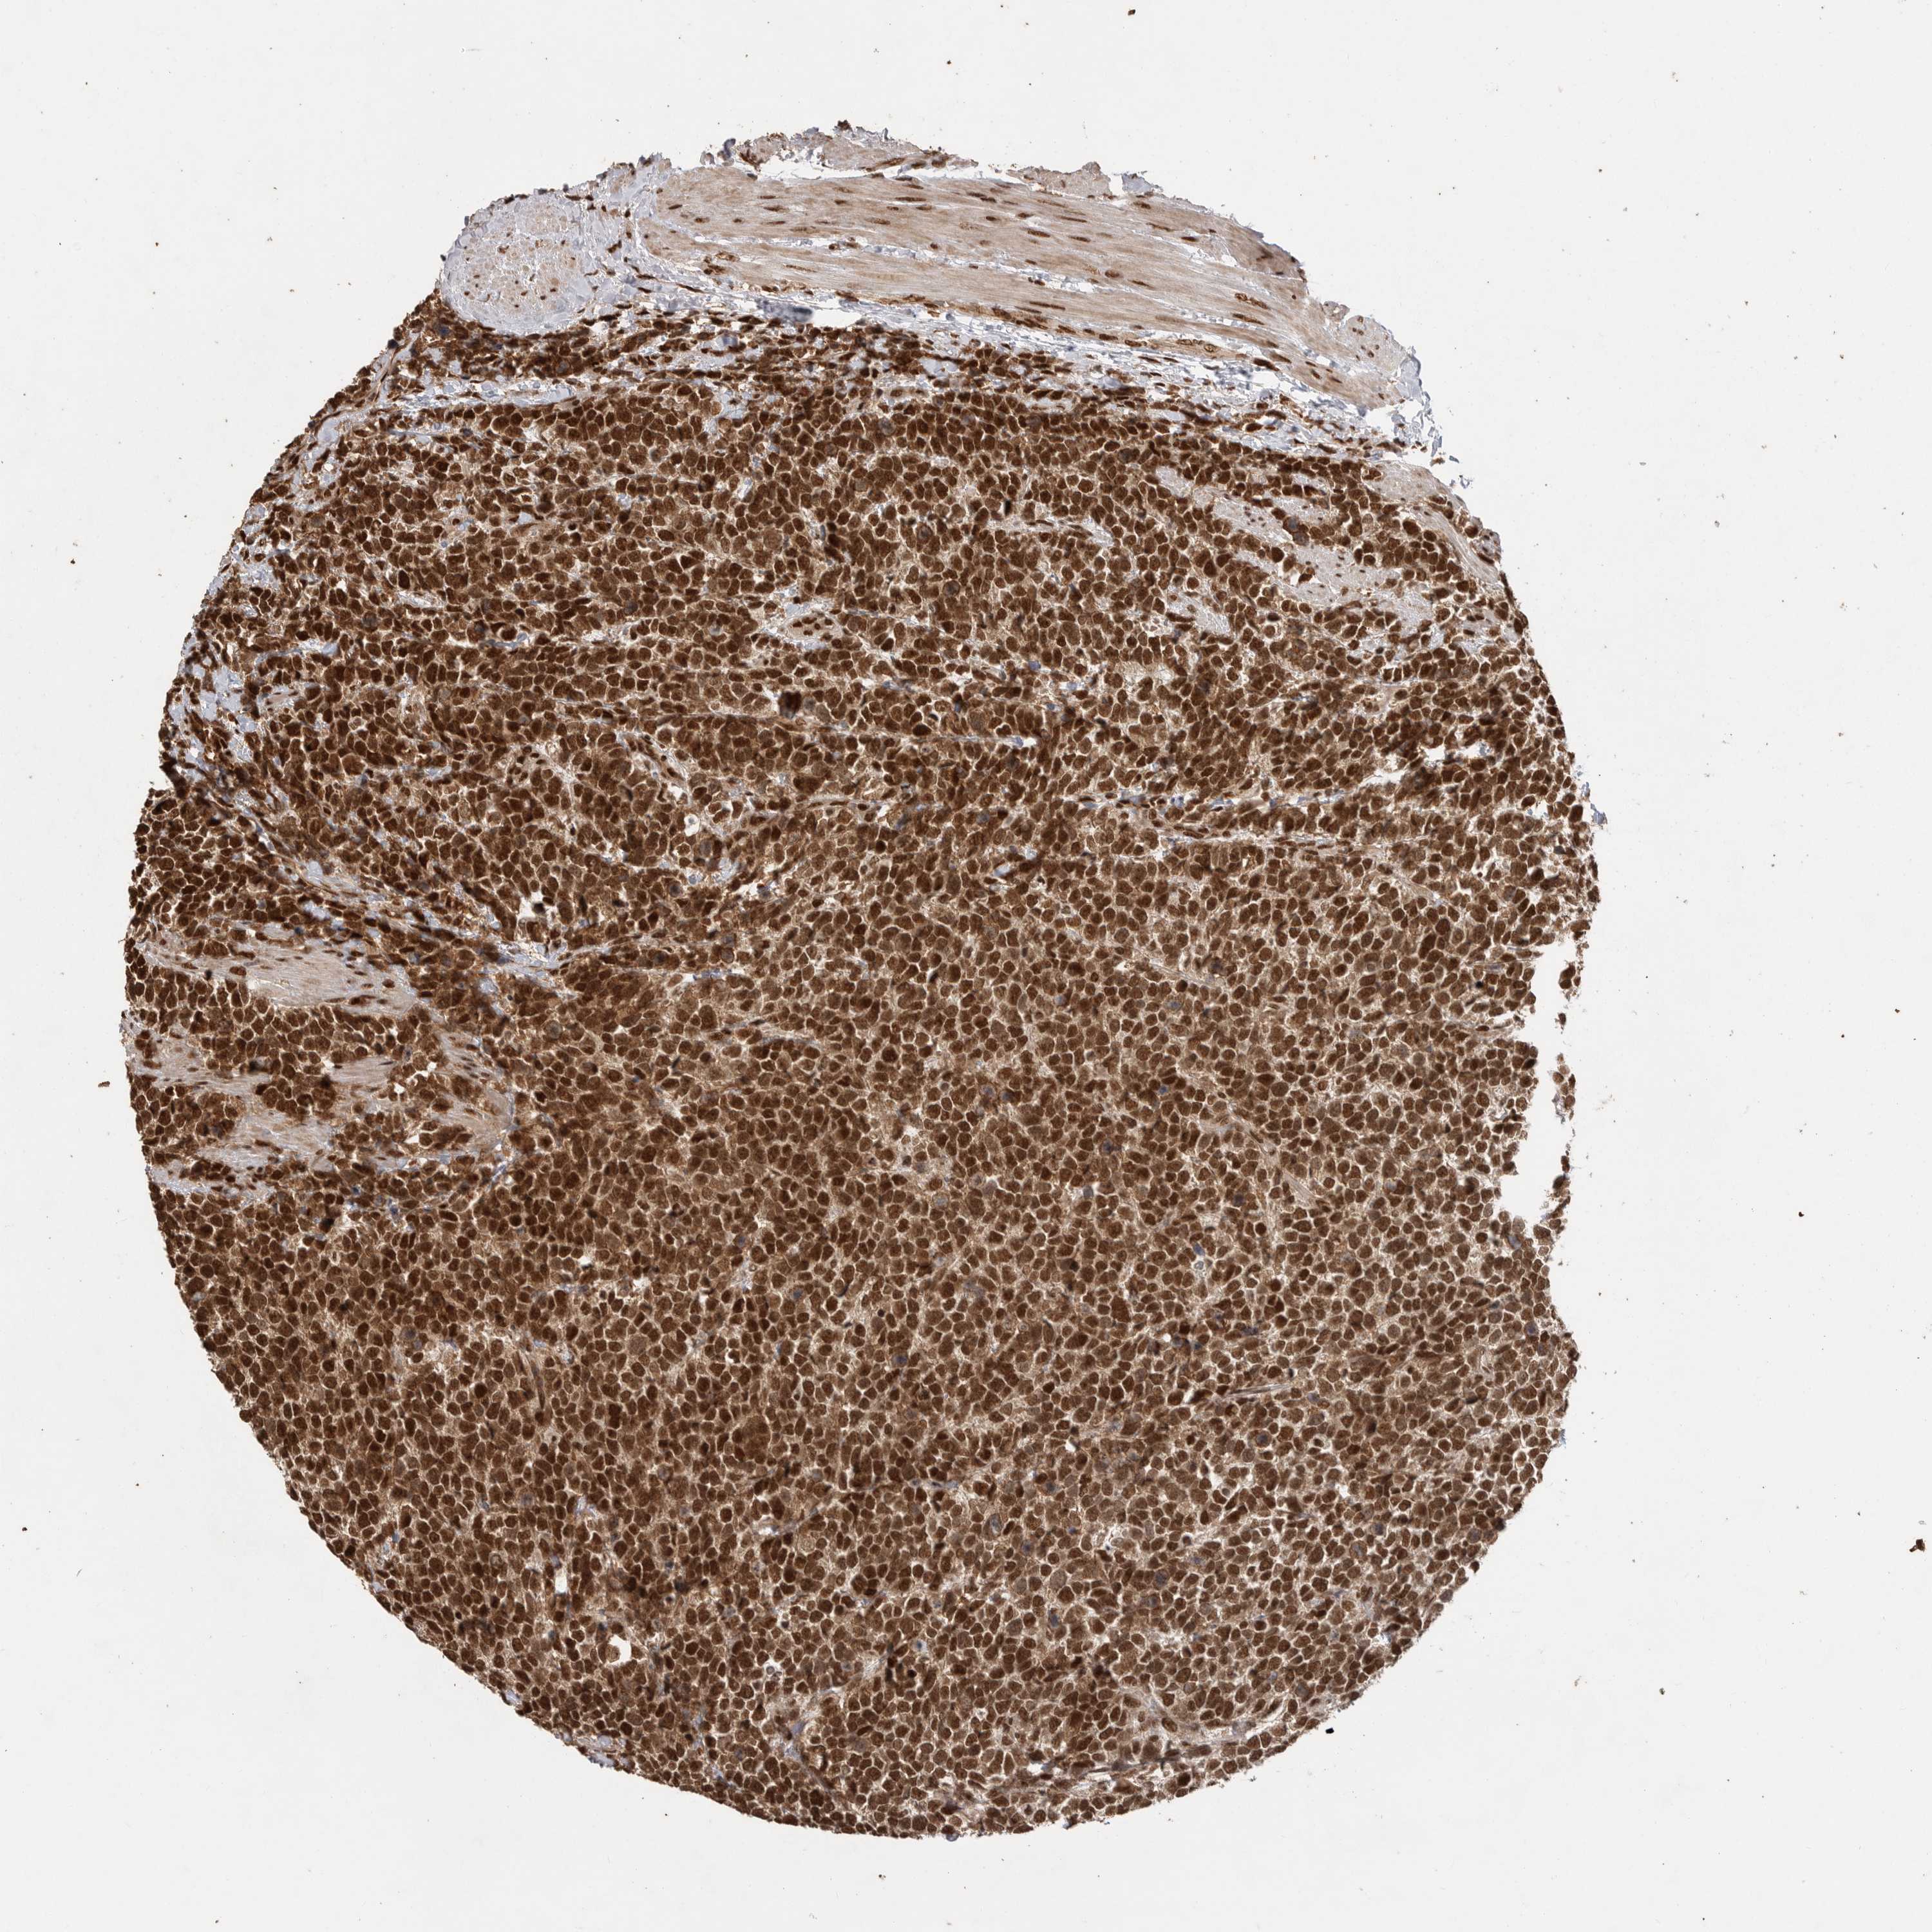

UROTHELIAL CANCER - Protein expressioni

A mouse-over function shows sample information and annotation data. Click on an image to view it in a full screen mode. Samples can be filtered based on level of antibody staining by selecting one or several of the following categories: high, medium, low and not detected. The assay and annotation is described here.

Note that samples used for immunohistochemistry by the Human Protein Atlas do not correspond to samples in the TCGA dataset.

Antibody stainingi

Antibody staining in the annotated cell types in the current human tissue is reported as not detected, low, medium, or high, based on conventional immunohistochemistry profiling in selected tissues. This score is based on the combination of the staining intensity and fraction of stained cells.

Each image is clickable and will lead to virtual microscopy that enables deeper exploration of all samples and also displays staining intensity scores, fraction scores and subcellular localization as well as patient and tissue information for each sample.

Antibody HPA027406

Antibody HPA027417

Antibody HPA027452

Urothelial carcinoma, Low grade

Urothelial carcinoma, High grade